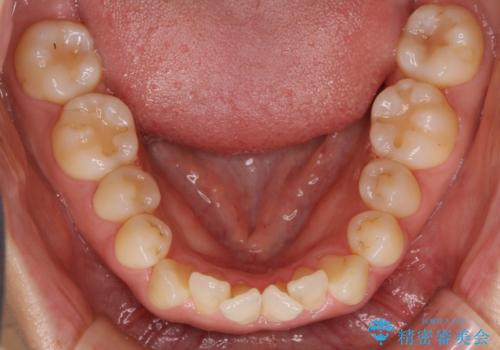

八重歯 上下の正中のずれ 40代で抜歯矯正

- 八重歯と上下の正中のずれを気にして来院。

上の前歯の正中が右にずれていました。

小臼歯抜歯を行い、ワイヤー矯正を行いました。

時間はかかりましたがしっかり治療することができました。